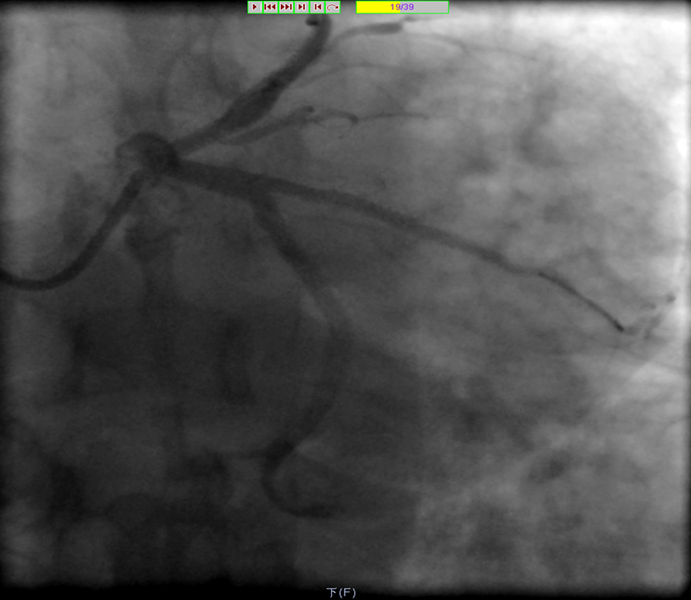

8月3日急诊PCI,术中造影

LAD近段可见血栓性完全闭塞(C).

OM近段可见钙化、弥漫性、偏心狭窄,程度90%。